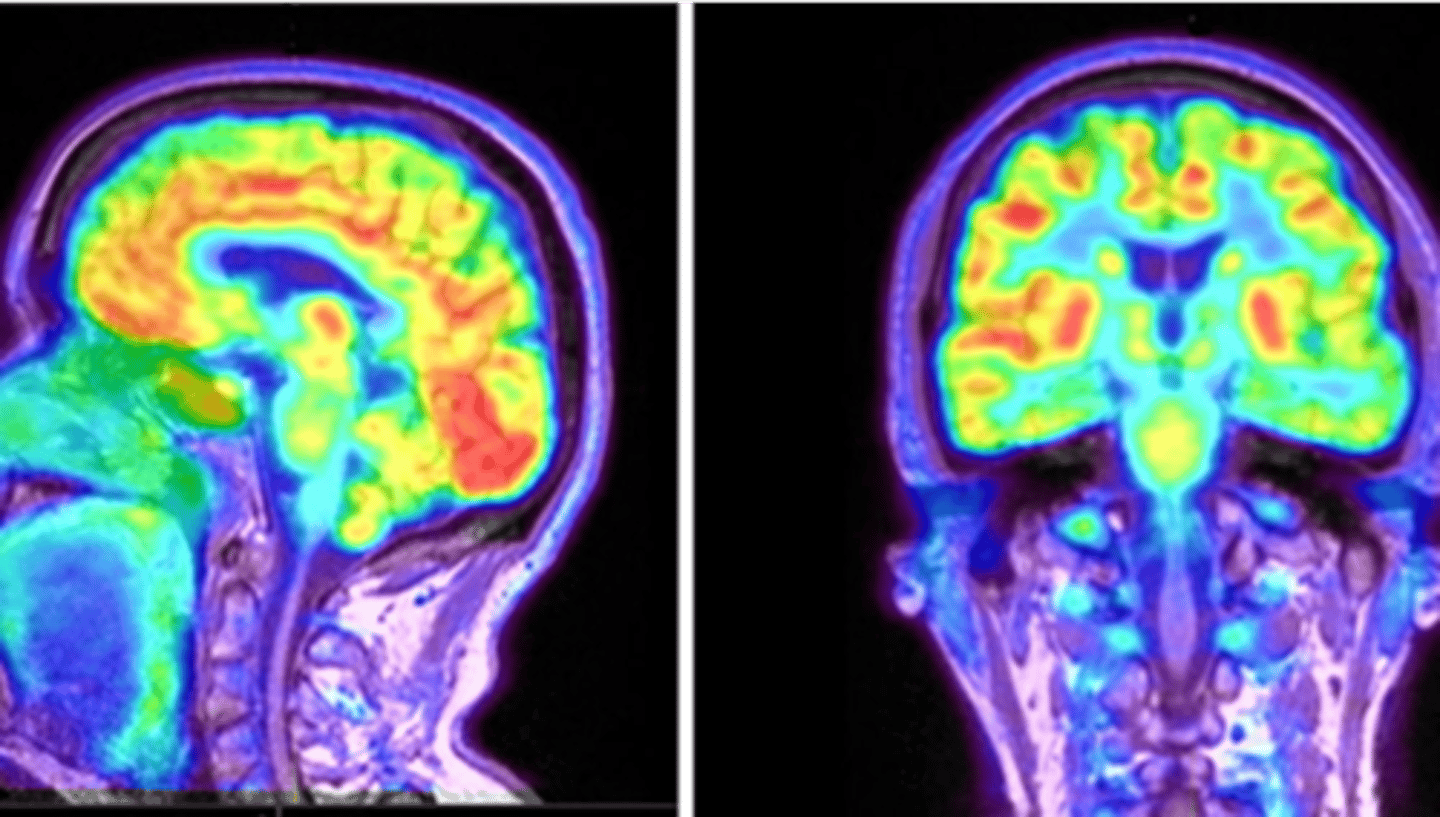

head PET Scans use ____ bound to glucose to show where the brain is _____

radioactive substance bound to glucose to see where the brain is working

PET Scans are used to identify brain

function

PET Scans are useful in evaluation of

alzheimer's disease, epilepsy, parkinson's disease, mets